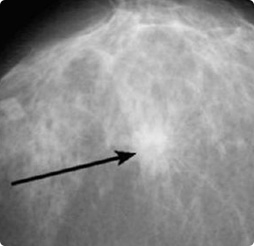

Маммограф МЭМ 20-08

Современный цифровой аппарат для диагностики заболеваний молочных желез с высоким качеством изображения. Обеспечивает комфортное обследование с минимальной лучевой нагрузкой. Оснащен удобной системой управления и регулируемыми параметрами. Подходит для различных видов маммографических исследований.

Цифровой маммограф МЭМ 20-08 - современное диагностическое оборудование для высокоточного обследования молочных желез. Аппарат разработан с учетом последних достижений в области медицинской визуализации и обеспечивает надежную диагностику различных патологий.